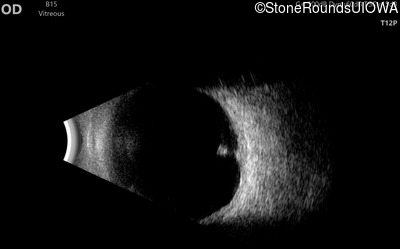

Visit at age: 12 years (Visit 2)

B-Scan Ultrasonography - Right - 20/600

Exemplar